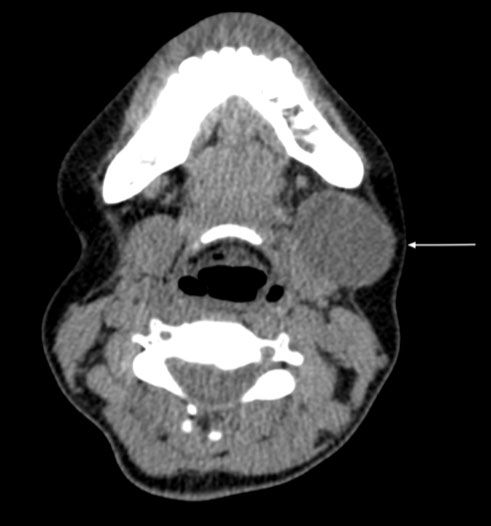

Contrast enhanced computed tomography imaging demonstrated a well-defined cystic lesion measuring 3.5 × 2.8 cm, positioned under the platysma and arising from the antero-lateral surface of the left submandibular gland, displacing the submandibular gland posteriorly (Figure 2). These findings led to a radiological diagnosis of a dermoid cyst of the submandibular gland. Fine needle aspiration cytology revealed an admixture of degenerate squamous cell and keratinous debris suggestive of an epidermoid cyst.

Figure 2: Contrast enhanced computed tomography imaging (axial view) showing the cystic lesion located anterior lateral to the submandibular gland beneath the platysma.